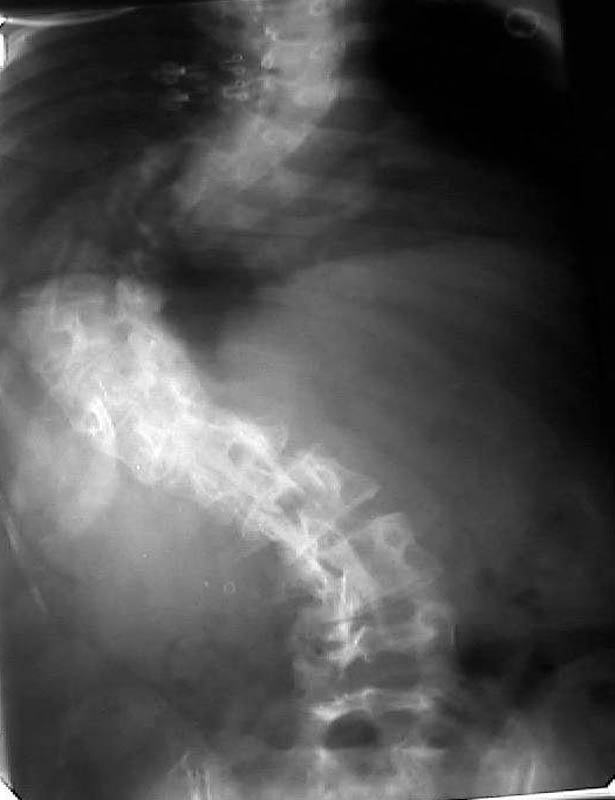

Мужчина, 38 лет. Двусторонний диспластический коксартрз, кифосколиоз.Правый сустав прооперирован 12.12.00, левый - в апреле 2003 г. Справа вывихнулась <чашка>.